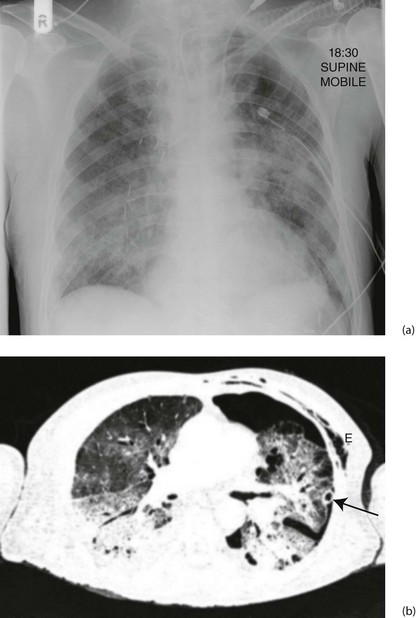

Fig. 12.5 Acute respiratory distress syndrome (ARDS)

(a) This middle-aged man underwent an oesophagectomy for carcinoma, with the proximal stomach anastomosed to the oesophageal remnant in the chest. He developed ARDS in the early postoperative period. The chest X-ray shows ill-defined alveolar opacification in the lung mid zones. Note the metallic vascular clips on the right side, the chest drain on the left side and the endotracheal tube and central venous line. (b) The CT scan shows bilateral consolidation in the dependent portion of both lungs with ‘ground glass’ opacification in the upper zones. There is a left pneumothorax with a chest drain in situ (arrowed); subcutaneous emphysema E resulting from the thoracotomy is also visible